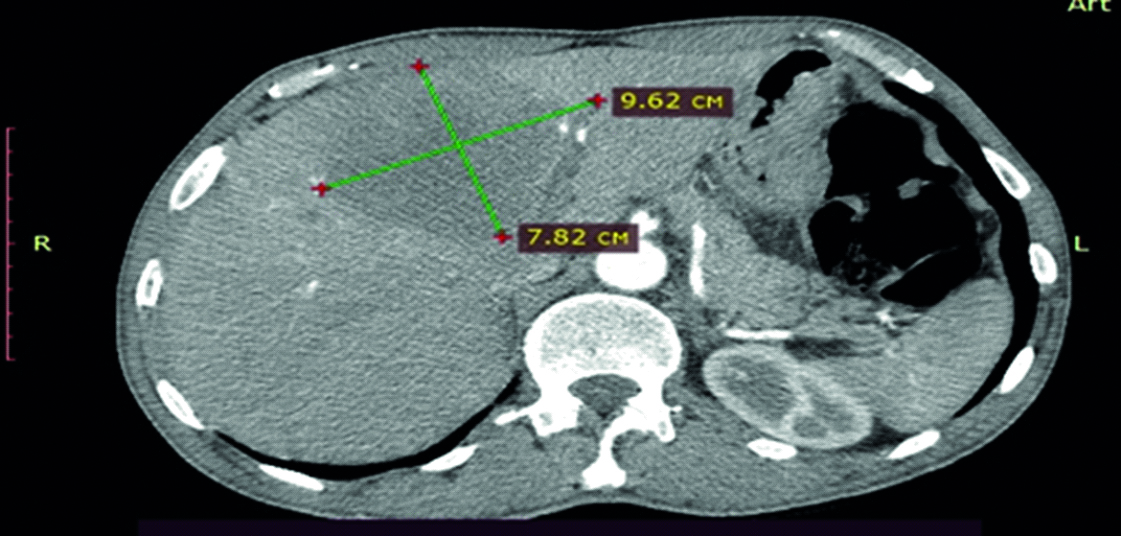

Findings of contrast-assisted computed tomography (CT) of the abdomen: the liver is of regular size, shape and position. Hepatic veins and branches of the portal vein are differentiated distinctly with no abnormalities. Density is without abnormalities. In the Segment IV (SIV) of the liver, there was identified an 86×84 mm hypovascular segment accumulating contrast (Fig. 2). On the border between SVIII and SVII, a 6×5 mm cyst is identified. Conclusion: solitary focus of metastasis to the liver.

Figure 2. Computed tomography. Metastasis focus in the left lobe of the liver (indicated by arrows).

Рисунок 2. Компьютерная томография. Очаг метастазирования в левой доле печени (указано стрелками).